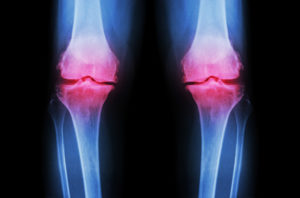

After a number of tests and X-rays, it was clear to Dr. X that his patient was in the early stages of osteoarthritis, a condition that is common with “wear and tear” of the joints, the aging process, repeated injury, and obesity.

He had ruled out inflammatory conditions by blood work analysis and a good physical exam and history. He took routine X-rays, which demonstrated mild degenerative changes and changes related to the thinning of cartilage and narrowing of joint spaces between the woman’s femur and tibia. These changes are typically seen in early osteoarthritis and chondromalacia (degeneration of the cartilaginous cushions of the joints).